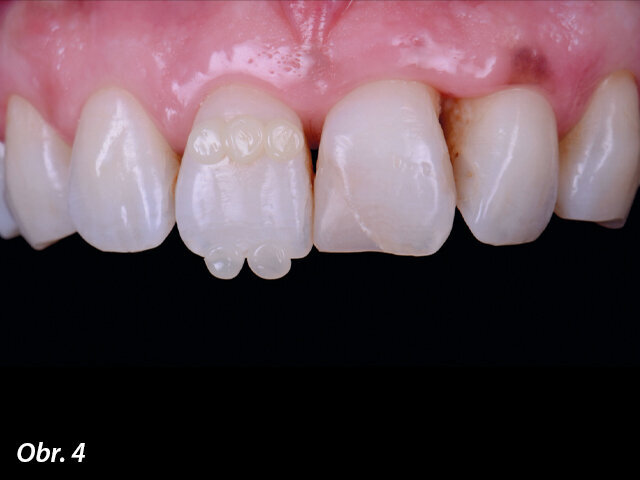

Výběr odstínu pomocí tzv. kompozitní „knoflíkové“ techniky (Composite Button Technique), s (4) a bez (5) polarizačních filtrů.